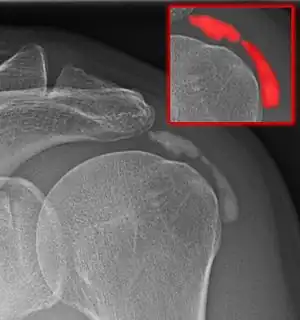

Calcific bursitis refers to calcium deposits within the bursae. This most occurs in the shoulder area. The most common bursa for calcific bursitis to occur is the subacromial bursa. A bursa is a small, fluid-filled sac that reduces friction, and facilitates movements between its adjacent tissues (i.e., between tendon and bone, two muscles or skin and bone). Inflammation of the bursae is called bursitis.

Diagnosis

Diagnostic methods are the following